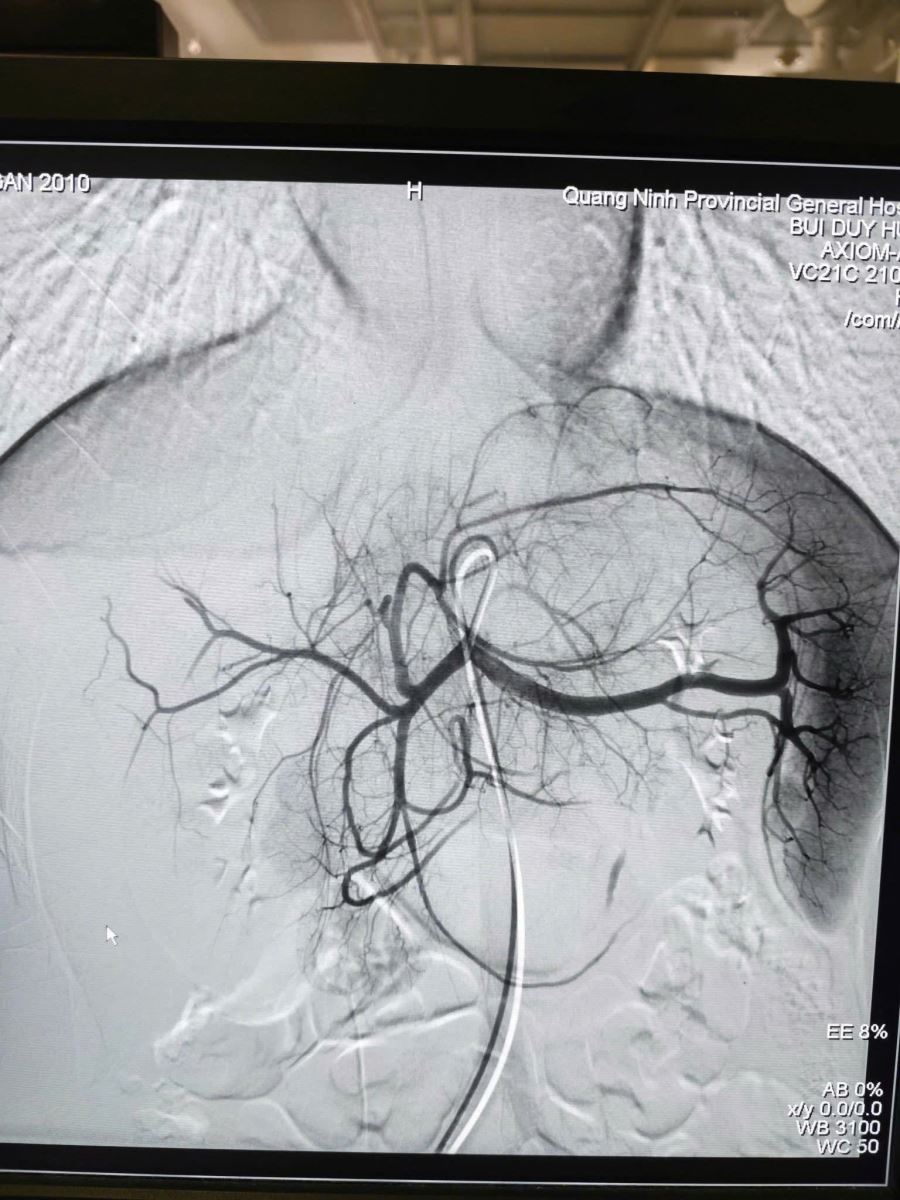

Hình tổn thương trên phim chụp DSA

Khi vận chuyển người bệnh về tại cơ sở chính, Ekip Can thiệp mạch đã sẵn sàng mọi nguồn lực. Ngay khi tiếp nhận, nhận thấy bệnh nhân có dấu hiệu thiếu máu, các bác sĩ đã chỉ định truyền máu kịp thời để bồi phụ tuần hoàn trước khi can thiệp. Dưới sự hỗ trợ của hệ thống DSA hiện đại, ekip bác sĩ đã luồn ống thông (Microcatheter) siêu nhỏ 1.9F tiếp cận siêu chọn lọc vị trí nhánh động mạch gan đang chảy máu và nút tắc bằng vật liệu chuyên dụng Spongel.

Ekíp can thiệp mạch do BSCKII Bùi Duy Hưng- Phó khoa Chẩn đoán hình ảnh – Điện quang can thiệp trực tiếp thực hiện